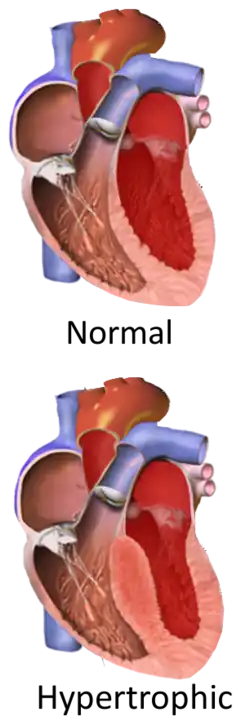

Hypertrophic cardiomyopathy (HCM, or HOCM when obstructive) is a condition in which muscle tissues of the heart become thickened without an obvious cause.[8] The parts of the heart most commonly affected are the interventricular septum and the ventricles.[10] This results in the heart being less able to pump blood effectively and also may cause electrical conduction problems.[3] Specifically, within the bundle branches that conduct impulses through the interventricular septum and into the Purkinje fibers, as these are responsible for the depolarization of contractile cells of both ventricles.[11]

Pathophysiology

Ventricular hypertrophy causes a dynamic pressure gradient across the left ventricular outflow tract (LVOT), which is associated with further narrowing of the outflow during systole. Pulling of the mitral valve leaflets towards the septum contributes to the outflow obstruction. This pulling is thought to occur by several proposed mechanisms, including that the flow of blood through the narrowed outflow tract results in it having a higher velocity, and less pressure through the Venturi effect.[17] This low pressure then causes the anterior leaflet of the mitral valve to be pulled into the outflow tract, resulting in further obstruction.[32]